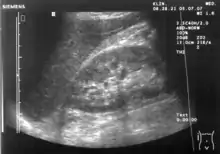

The hepatorenal recess[1] (subhepatic recess, pouch of Morison or Morison's pouch) is the subhepatic space that separates the liver from the right kidney. As a potential space, the recess is not normally filled with fluid. However, fluid can collect here in circumstances where the abdomen fills with fluid, such as hemoperitoneum. This fluid may be seen on ultrasound or computed tomography (CT scan).

Since it is a potential space, the hepatorenal recess is not normally filled with fluid. However, this space becomes significant in conditions in which fluid collects within the abdomen (most commonly ascites and hemoperitoneum). The intraperitoneal fluid, be it blood, ascites, or dialysate, collects in this space and may be visualized, most commonly via ultrasound or computed tomography (CT) scanning. As little as 30 or 40 ml of fluid in the abdominal cavity may be visualized in this space.

Early visualization of fluid in the hepatorenal recess on FAST scan may be an indication for urgent laparotomy.[2]